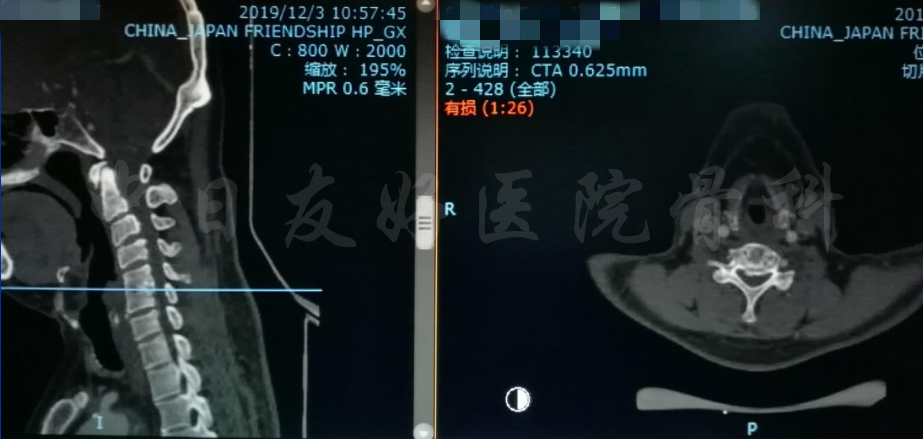

影像学检查

颈椎X片

颈椎MRI

颈椎MRI

颈椎各节段MRI(上下滑动)

颈CT(上下滑动)

腰椎MRI